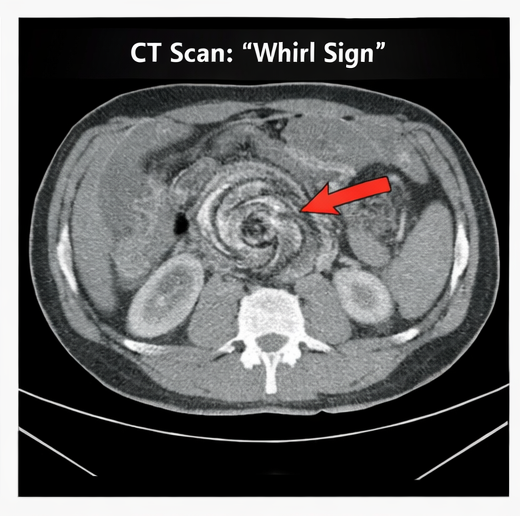

The classic presentation includes abdominal distension, abdominal pain, constipation, and vomiting. Radiological evaluation plays a critical role in diagnosis. Plain abdominal radiographs often demonstrate the coffee bean sign, while CT imaging provides more detailed visualization, including the whirl sign of twisted mesenteric vessels.

Radiological findings including the characteristic coffee bean sign on abdominal X-ray and the whirl sign on CT scan play a crucial role in confirming the diagnosis and guiding treatment decisions. Initial management focuses on patient stabilization through fluid resuscitation, gastrointestinal decompression, and correction of electrolyte imbalances.